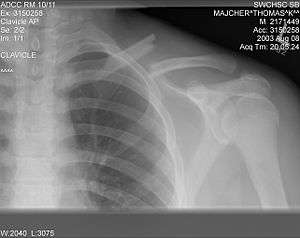

| X-ray of a left clavicle fracture | |

The basic method to check for a clavicle fracture is by an X-ray of the clavicle to determine the fracture type and extent of injury. In former times, X-rays were taken of both clavicle bones for comparison purposes. Due to the curved shape in a tilted plane X-rays are typically oriented with ~15° upwards facing tilt from the front. In more severe cases, a computerized tomography (CAT) or magnetic resonance imaging (MRI) scan is taken. However, the standard method of diagnosis through ultrasound imaging performed in the emergency room may be equally accurate in children.[1]